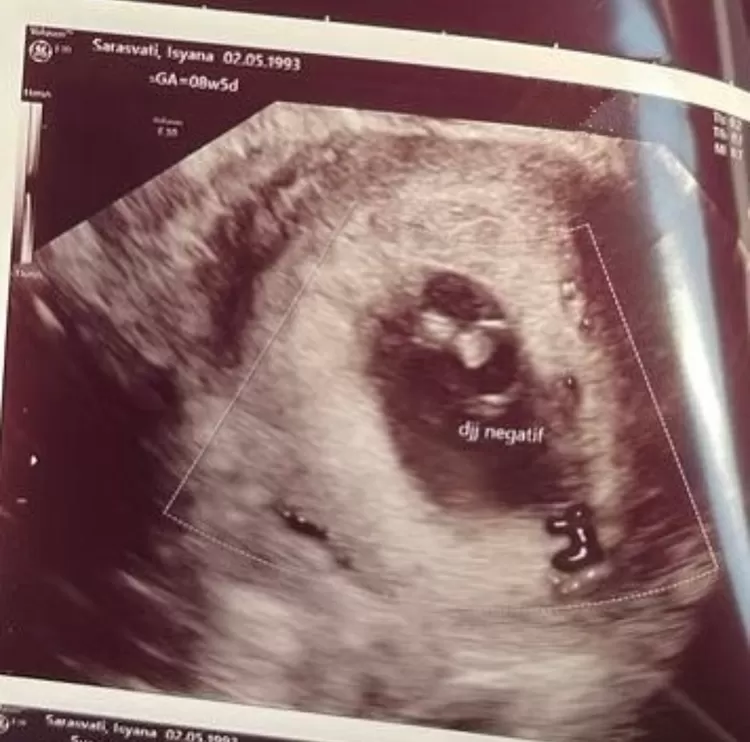

GORAJUARA - Isyana Sarasvati mengungkapkan alami keguguran. Kabar duka itu ia sampaikan melalui unggahan di media sosial pada Selasa (10/10) dengan mengunggah emotikon bunga mawar gugur, serta hasil USG kandungannya.

"Sampai berjumpa lagi bebinyo. Terima kasih sudah mau berjuang bersama-sama. We'll see you again, till the day our paths cross, we love you so so much bebinyo," tulis Isyana dengan emotikon menangis, malaikat, dan hati putih.